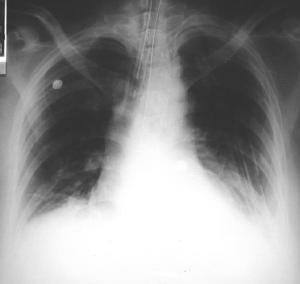

• Radiología del Tórax

Rx. tórax. PA y Lateral Izquierda

Rx. Tórax al momento de su Ingreso. radiopacidad difusa del hemitorax izquierdo conteniendo asas delgadas dilatadas con edema de la pared intestinal, desviación mediastinica contra lateral, disminuyendo por compresión del volumen torácico derecho, en la Rx lateral imágenes de niveles hidro-aereos múltiples , con discontinuidad diafragmática izquierda.